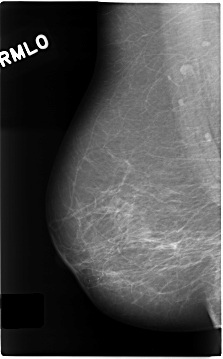

C_0146_1.RIGHT_MLO

RIGHT_MLO LINES 4656 PIXELS_PER_LINE 2888 BITS_PER_PIXEL 12 RESOLUTION 50 NON_OVERLAY